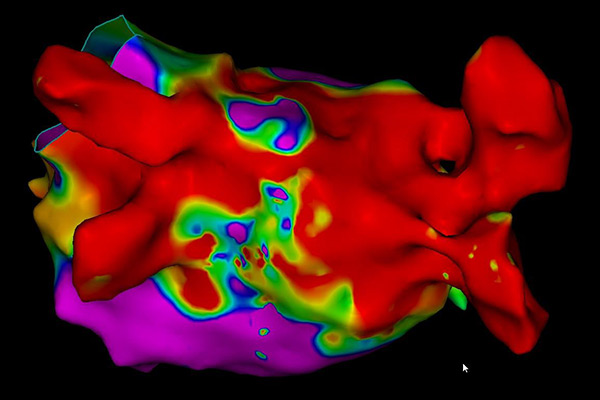

При електрофизиологичното изследване, посредством катетри (представляващи малки тръбички, които записват електрически сигнали) се прави точен запис на електрическите импулси в сърцето.

Изследването се извършва в т.нар. електрофизиологична лаборатория, в която се намира оборудването, необходимо за извършване на процедурата. В зависимост от аритмията се използва местна упойка, като при някои процедури се предпочита обща упойка (Вашият лекуващ лекар ще Ви уведоми за вида упойка, която ще бъде използвана). През вена на десния крак (понякога се налага използването на артерия) се въвеждат специални катетри (тръбички с диаметър под 3 мм), които записват директно електрическите сигнали от сърцето. По време на самото изследване сърцето се стимулира с електрически импулси, които Вие може да усетите като сърцебиене или по-силни сърдечни удари.

След като Вашият лекар е локализирал виновното за Вашата аритмия огнище се преминава към лечение – аблация. Посредством специален катетър се прилага енергия, наречена радиофреквентна енергия, която води до загряване и изгаряне на това огнище. Освен нагряване, при някои аритмии се използват специално пригодени балони или катетри, чрез които се постига замразяване на огнищата, водещи до аритмия, и тяхното елиминиране.